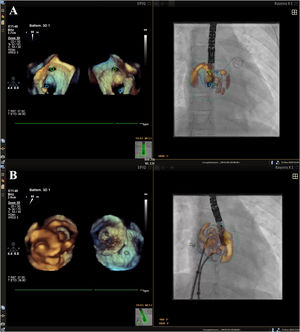

- Echocardiographic-fluoroscopic fusion imaging with the mini 3D transesophageal probe in pediatric congenital heart disease

- Ramona Ghenghea, Khaled Hadeed, Paul Vignaud-Marighetto, Nicolas Combes, Philippe Acar, Clement Karsenty

- Rev Esp Cardiol. 2026;79:85-8